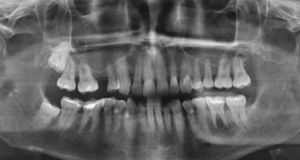

En la ortopantomografía de este paciente se observa una zona hipodensa localizada (aclaramiento) perirradicular en el diente 36 (fig. 1). La estructura mencionada abarca desde el ápice mesial del diente 37 hasta el ápice del diente 35. En la tomografía volumétrica dental adquirida consecutivamente, la masa hipodensa ocupante del espacio se extiende hacia caudal hasta el conducto mandibular del lado izquierdo y hacia bucal hasta el hueso compacto bucal (figs. 2 y 3). Este presenta dos perforaciones ovales a la altura del diente 36 (fig. 4). El techo del conducto mandibular del lado izquierdo no es apreciable en un tramo de aproximadamente 7mm. Se observan íntegramente las raíces de los dientes 35, 36 y 37.